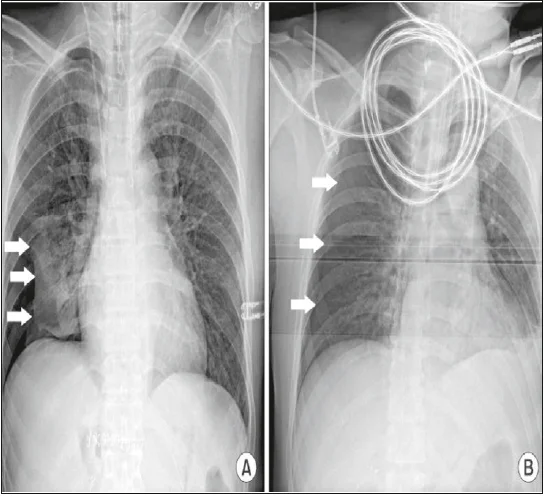

Лікувальні дії: припинення операції, негайна десуфляція, проведення рентгенографії легень, дренування плевральної порожнини (рис. 24, 25).

Рис. 24. Правобічний пневмоторакс на рентгенограмі грудної клітки: стрілками вказана вісцеральна плевра, що покриває праву легеню